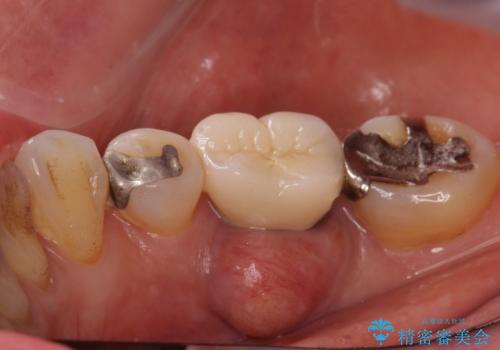

- 歯茎が腫れて痛いとの事で来院。

保存できない状態でしたので抜歯をして歯槽堤保存術を行いました。その後大臼歯部にインプラント治療を行いました。

また1番奥の歯はセラミックインレーで治療を行いました。